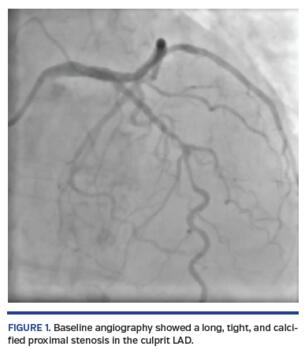

A short, 81-year-old woman presented with non-ST elevation acute myocardial infarction complicated with acute pulmonary edema. She was referred to urgent coronary angiography, performed via right distal transradial access, which is our default approach. The culprit left anterior descending (LAD) coronary artery was shown to have a long, tight, and calcified proximal-mid stenosis (Figure 1; Video 1), which was fixed by PCI with two drug-eluting stents (3 x 33 mm and 3.5 x 33 mm), requiring adequate pre- and postdilations with non-compliant balloons (2.5 x 20 mm and 3.5 x 20 mm, respectively). Surprisingly, the final angiogram showed an unexpected huge cavity spilling in-stent mid LAD perforation, with drainage to the left ventricle (Figure 2; Video 2). Promptly, the same postdilation NC 3.5 x 20 mm balloon was reinflated to 8 atm at the level of the CAP. After 10 minutes, there was some resolution. After a total 20 minutes of persistent balloon inflation without anticoagulation reversal, a final angiogram confirmed the CAP had been completely sealed without any residual contrast extravasation (Figure 3; Video 3). Transthoracic echocardiogram discharged pericardial effusion.